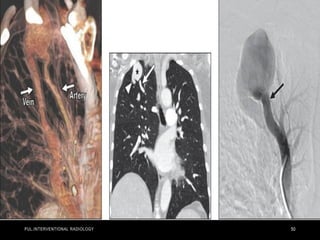

DIAGNOSTIC TESTING – pulmonary angiography

• Pulmonary angiography generally is no longer necessary as a

diagnostic procedure alone.

• It is reserved for therapeutic purposes after a diagnosis has

been established.

• It remains the gold standard for inconclusive cases.

• Percutaneous TCE is the gold standard for the treatment of

PAVM because it is effective in reducing the risk of paradoxical

embolism and other complications associated with PAVM.

• less invasive and easy to repeat .

• disadvantages include collateralization and revascularization

• During embolization, the supplying artery immediately preceding

the PAVM is the target to occlude the feeding vessel just

proximal to the aneurysmal sac .

• The deployed coils are designed to coil within the vessel lumen

and carry micro fibers that activate platelets to generate an

occluding platelet plug.

• Amplatzer vascular plugs (AVPs) and balloon devices provide

direct obstruction to vascular flow.